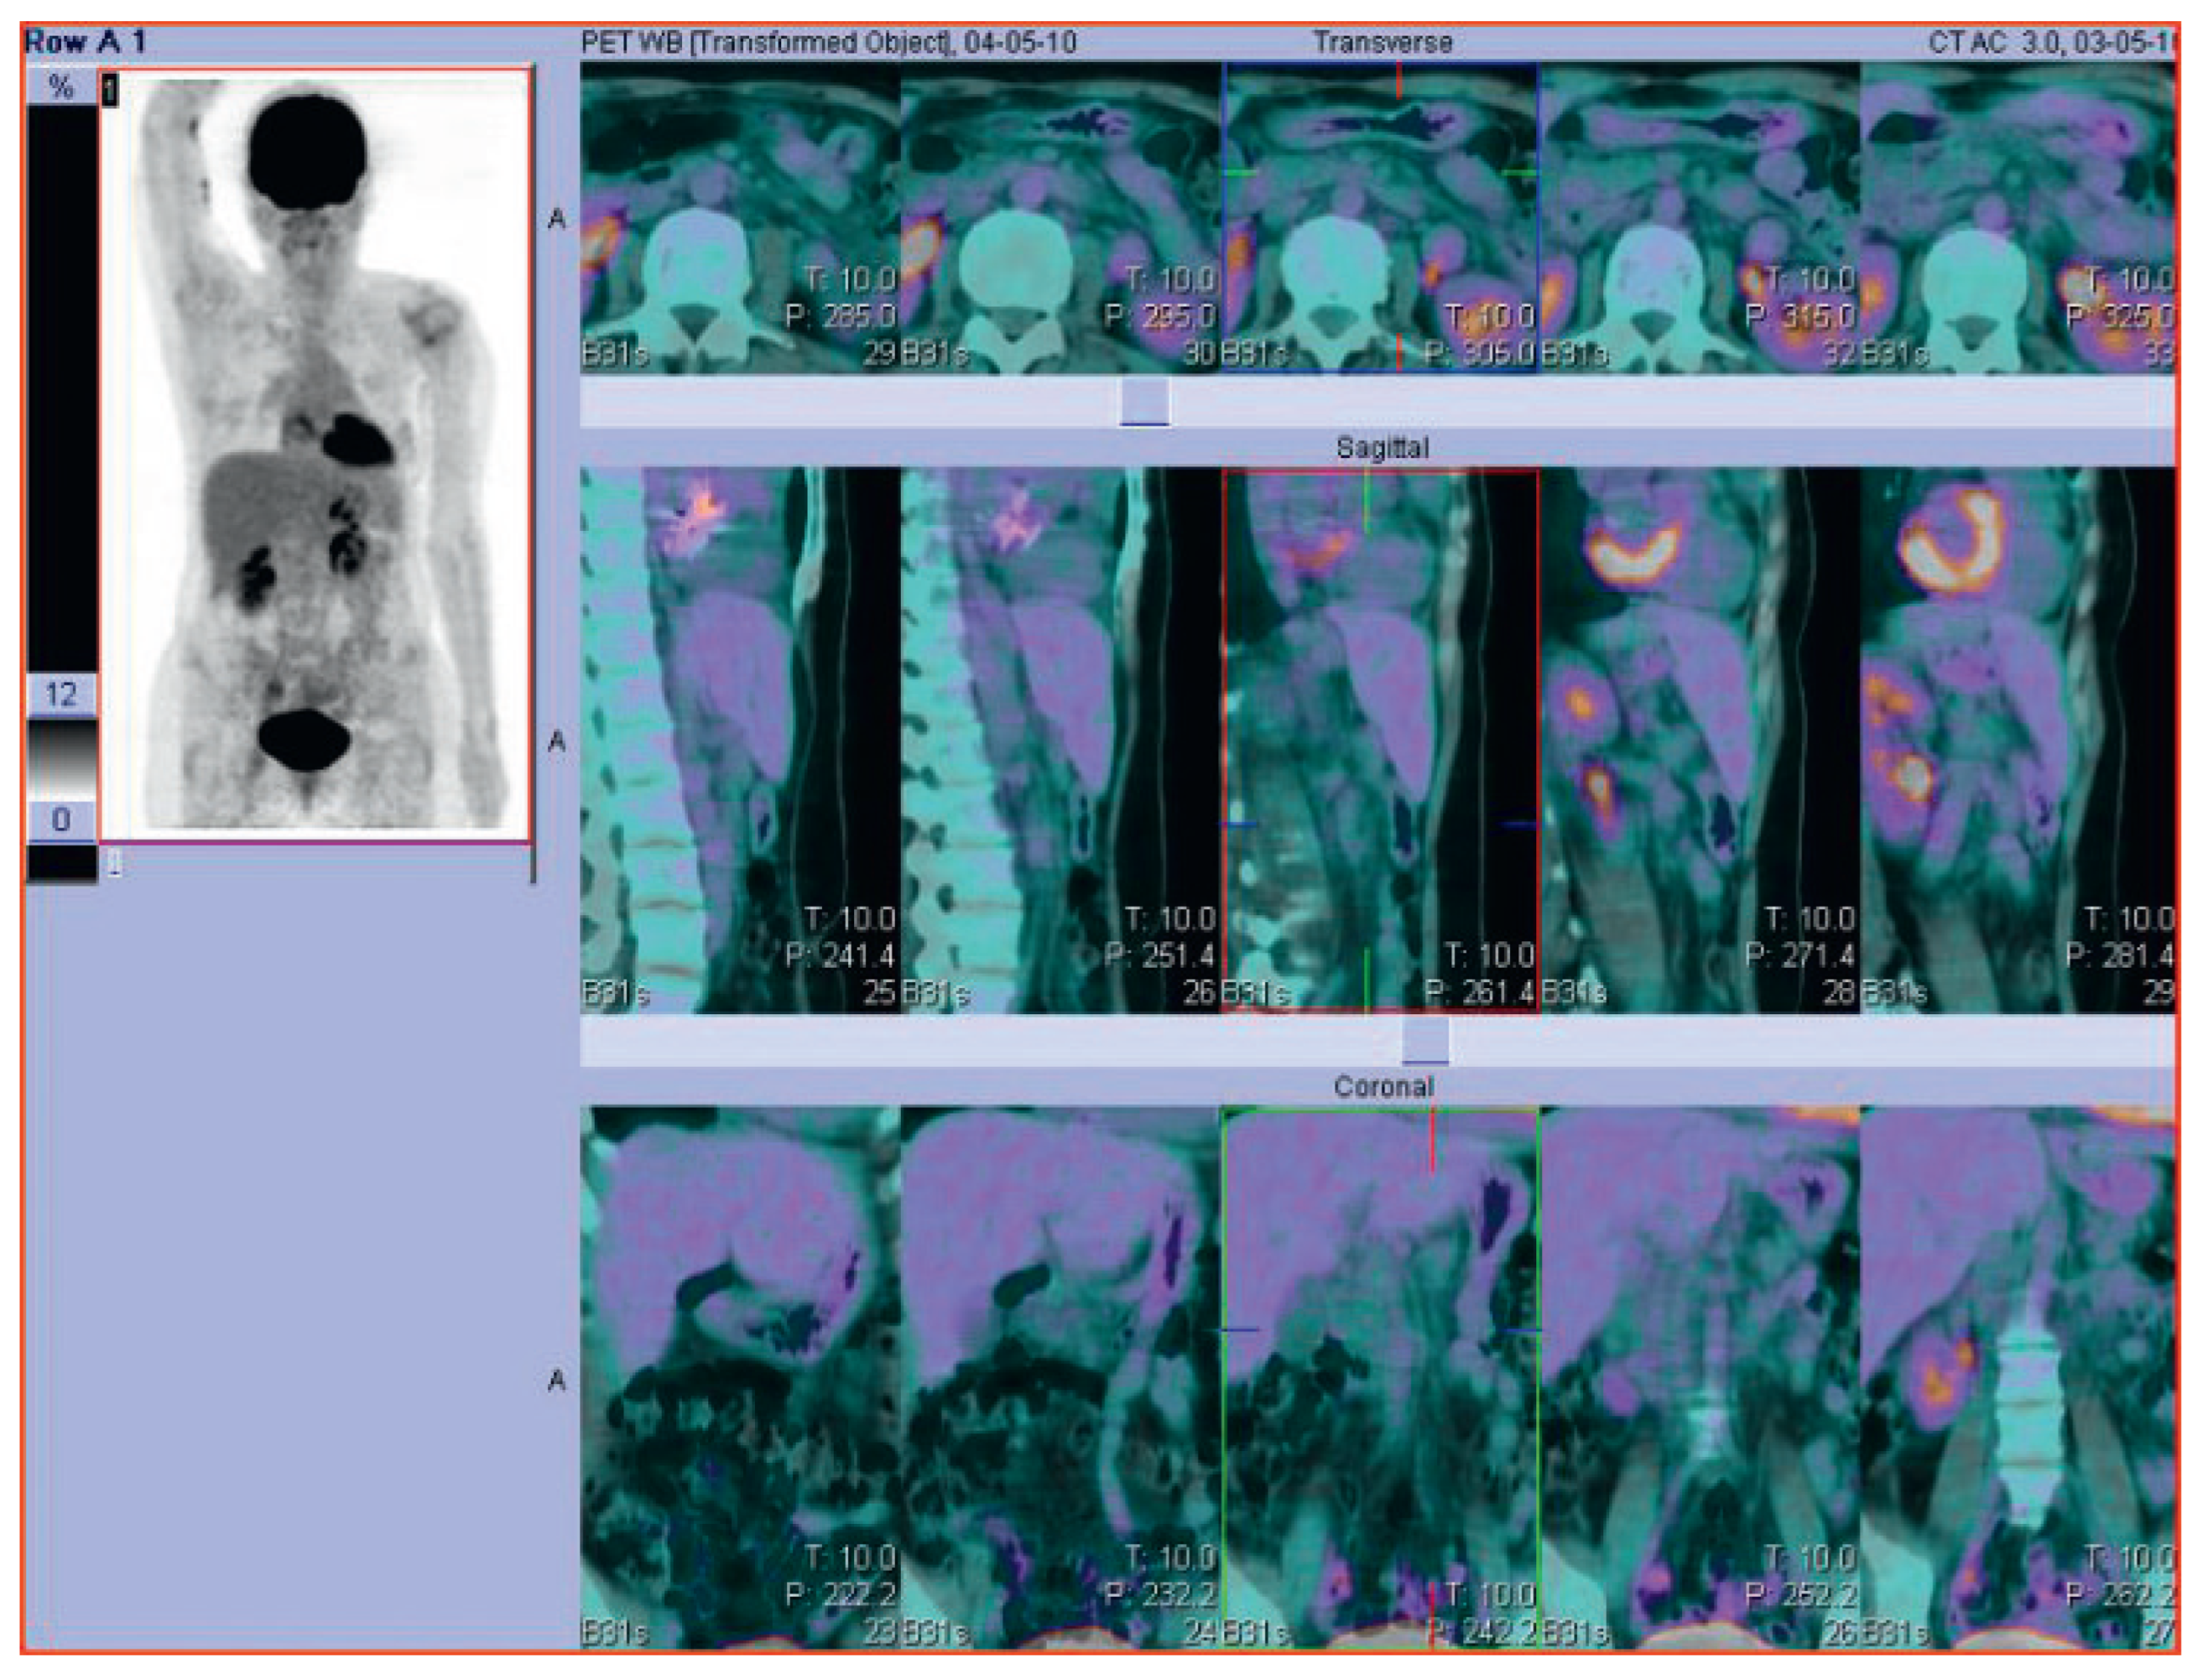

Cardiac complications in a patient with Hodgkin lymphoma—a case report

Figure 2. Follow-up PET-CT scan of the same patient with Hodgkin Lymphoma after successful treatment.